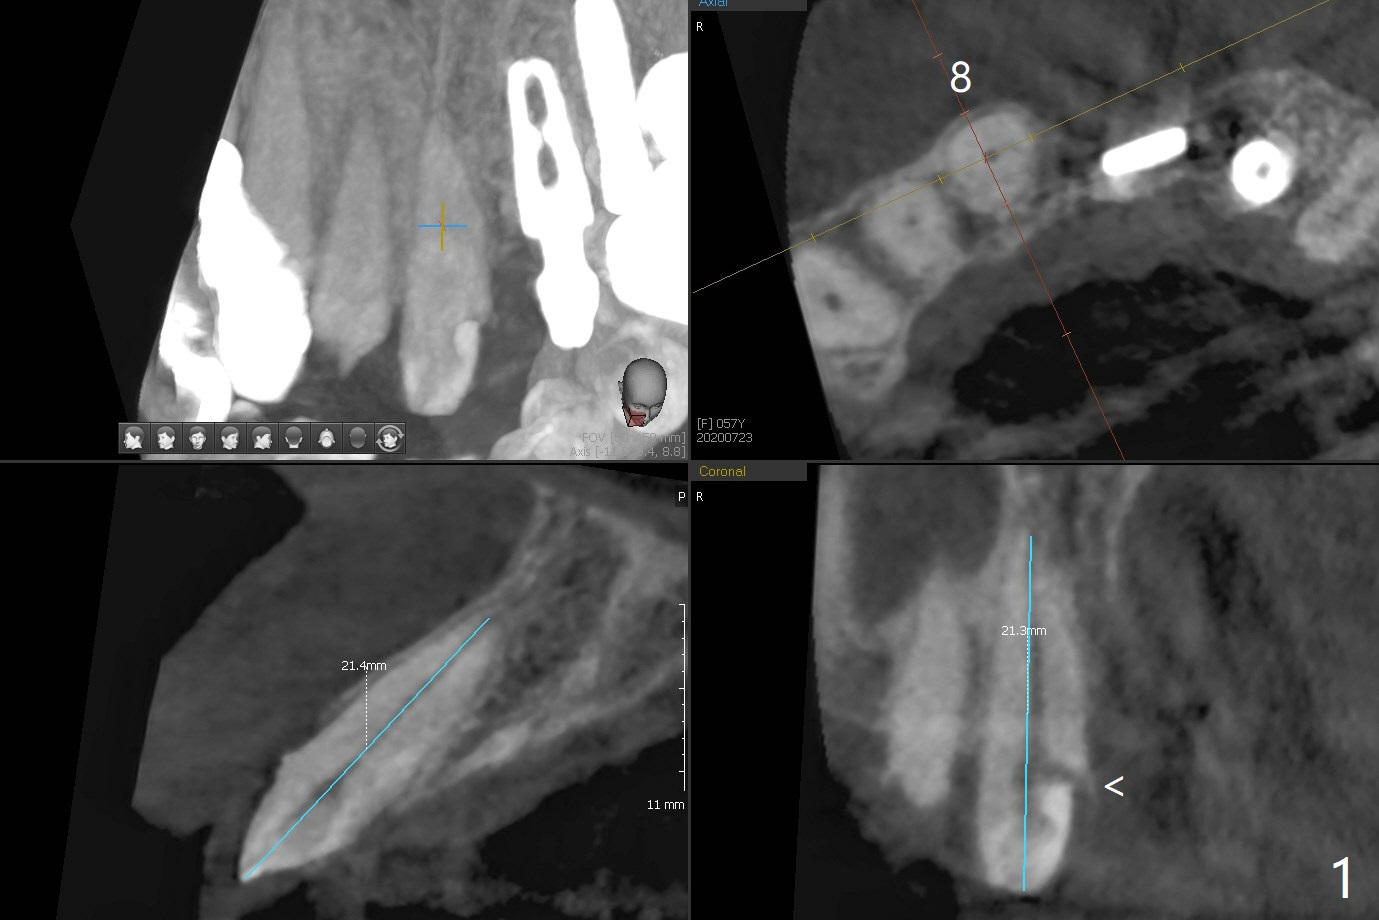

58岁女前牙桥撤除后三个月右上1(8号牙)出现牙髓炎,利用三个月前拍摄CT测定工作长度21.5毫米(图一),与术中根尖测定仪一致,但是40/.04 master cone没有达到工作长度(图二),再次使用根尖测定仪,工作长度22毫米,master cone空管临床上好像达到工作长度,但是加上糊剂,master cone临床上仍然不到工作长度,与根尖片一致(图三),三次切除牙胶尖,三次垂直压缩,仍然没有缓解长度问题(图四)。但愿临床上没有问题,此例是活髓。最终牙冠应用临时粘固剂。如果使用细的牙胶尖(考虑年龄因素),例如30/.04,可能简单些。